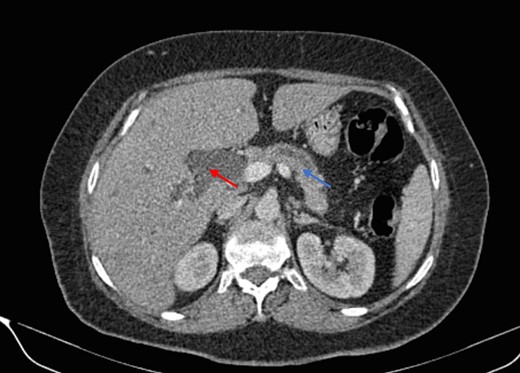

Mr. A. is a 65-year-old hypertensive patient presenting with acute epigastric pain associated with abdominal bloating. Biological settings showed amylasemia at 450 IU/L and lipasemia at 525 IU/L. Abdominal CT scan revealed heterogenous poorly defined mass in the pancreatic head with low enhancement (Figs 1 and 2). The CA 19–9 assay was 280 IU/L. Cephalic duodenopancreatectomy was performed. Histological examination of the operative specimen revealed a solid, trabecular, undifferentiated carcinomatous process (Fig. 3) expressing markers (CK(AE1-AE3) and p40) (Fig. 4), confirming the diagnosis of primary squamous cell carcinoma of the pancreas. The extension study showed no secondary localization.

Low-enhancing poorly defined mass in the pancreatic head with surrounding fat stranding (arrow).

Parenchymal atrophic changes and main pancreatic duct dilatation distal to the mass (blue arrow). Extra and intrahepatic bile ducts are dilated (red arrow).